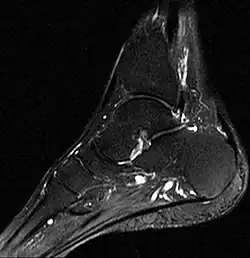

- Fuß, MRT, T2-Gewichtung

-

Knochenmarködem (hell) in Sprungbein, Kahnbein und Keilbein -